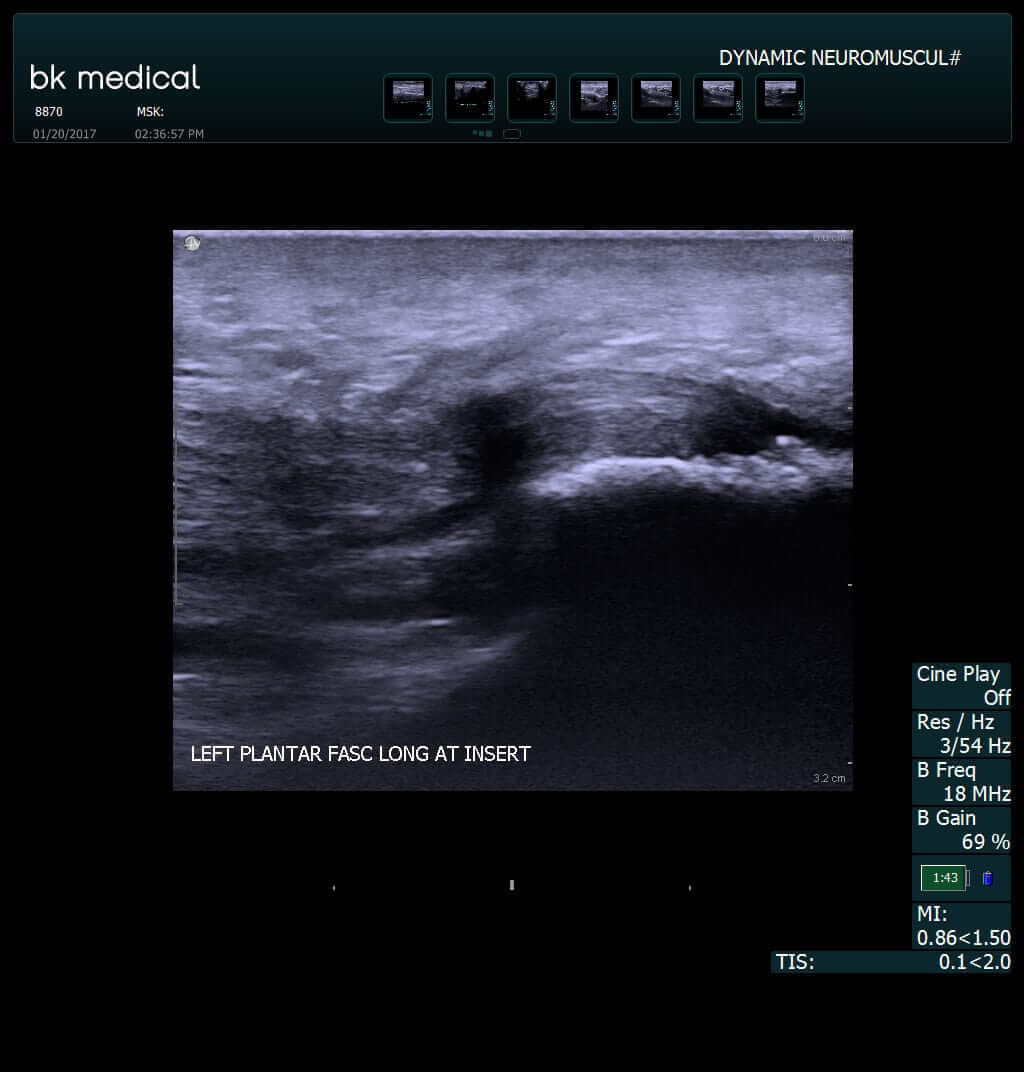

A number of differential diagnoses for pf exist including baxter�s nerve compression, tarsal tunnel syndrome, calcaneal stress fracture and plantar fascia rupture [83, 84]. Plantar fasciitis (pf) is defined as a painful heel with inflammation of the plantar fascia (lemont, ammirati & usen, 2003). Volume of ambulatory care visits and patterns of care for patients diagnosed with plantar fasciitis: Podomania, apr 3, 2011, in forum: And that thickness values >4.0 mm are diagnostic of plantar fasciitis.

• or the patient who looked up their symptoms online, so. The differential diagnosis of heel pain is extensive, but a mechanical etiology is the most common. And that thickness values >4.0 mm are diagnostic of plantar fasciitis. Accordingly, this author reviews pertinent keys to the patient history, physical exam and diagnostic testing that can help facilitate an accurate diagnosis. Its characteristic features are pain and tenderness, predominately on the medial aspect of the calcaneus near the sole of the heel.